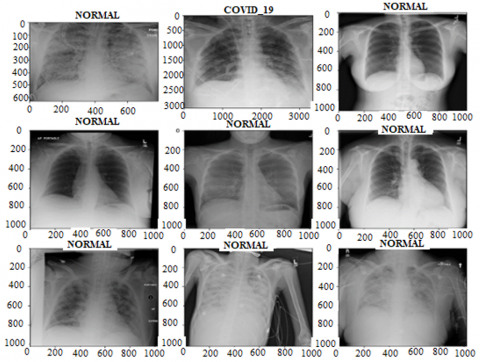

Furthermore, Figure 3 displays a compilation of chest X-ray images retrieved from selected databases. It demonstrates both normal chest X-ray images and a sample of a diseased chest X-ray, specifically from the COVID-19 class.

Figure 3. Samples from the datasets showing normal and diseased X-rays